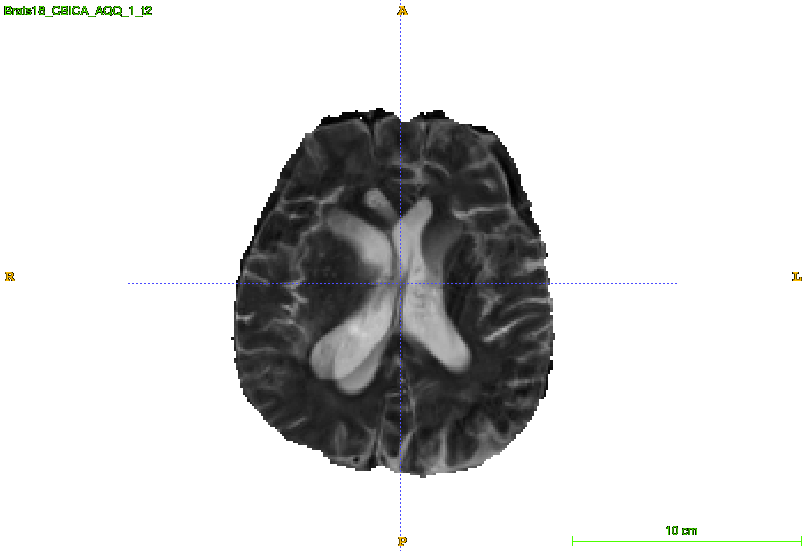

MRI analysis takes central position in brain tumor diagnosis and treatment, thus it’s precise evaluation is crucially important. However, it’s 3D nature imposes several challenges, so the analysis is often performed on 2D projections that reduces the complexity, but increases bias. On the other hand, time consuming 3D evaluation, like, segmentation, is able to provide precise estimation of a number of valuable spatial characteristics, giving us understanding about the course of the disease.

Since MRI scans are the set of multiple three dimensional arrays, it’s manual analysis and evaluation is a non-trivial procedure and requires time, attention and expertise. Lack of these resources can lead to unsatisfying results. Typically, these scans are analyzed by clinical experts using two dimensional cut and projection planes. It limits the amount of data taken into account for decision making, this it adds bias to the resulting evaluation. On the other hand, accurate segmentation and 3D reconstruction is able to provide more insights on disease progression and help a therapist to plan the treatment better. However these methods are not widely used due to unreasonable amount of time needed for manual labeling.

During training we randomly flip input image along sagittal plane and ”mute” input modalities with predefined probability. Without this augmentation the network was only considering one of the input modalities while making a prediction and not taking others into account. To deal with this issue we are randomly filling input channels with Gaussian noise. We introduce probability to apply this augmentation for every channel and set it to 0.1, so there is 34% chance to mute at least one out of four modalities. This also helps to aggregate information allover input data and to deal with noisy or corrupted input images like illustrated in the picture 4.